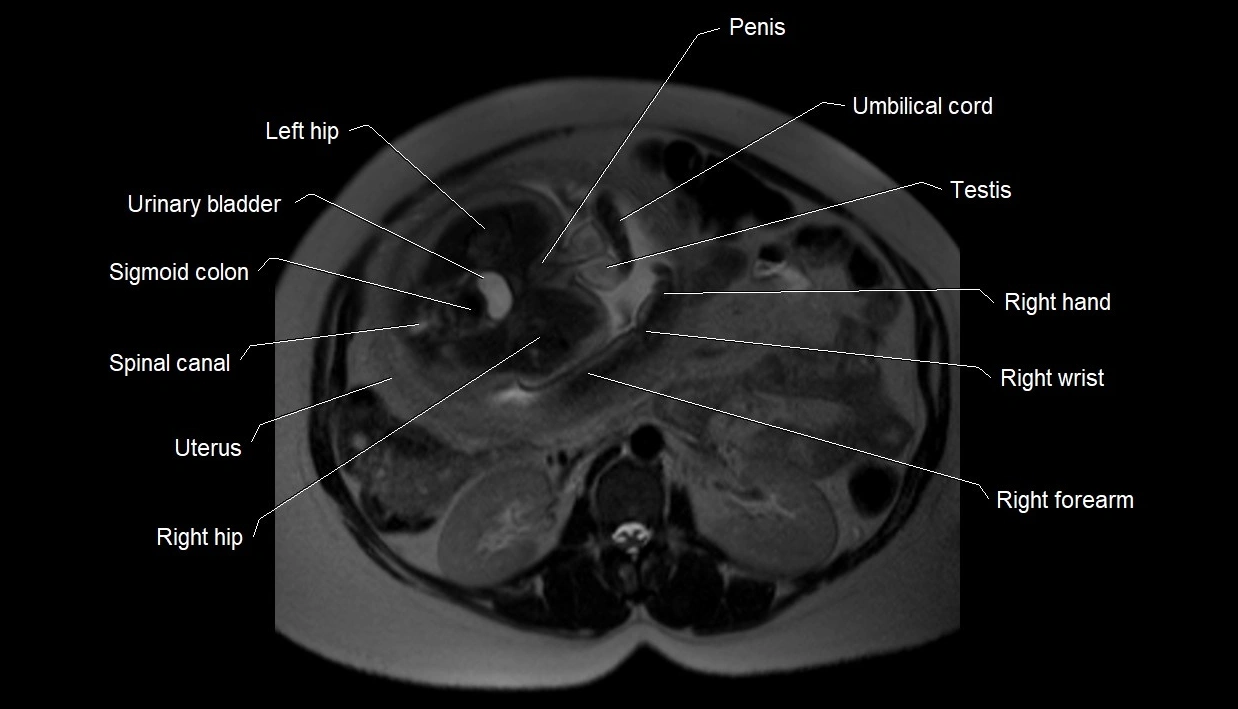

MRI Appearance

T2 HASTE (T2 GRE):

• Amniotic fluid shows very bright hyperintense signal

• Provides natural contrast against fetus and placenta

• Small particles (vernix) may appear as scattered hypointense foci within bright fluid

MRI image

image